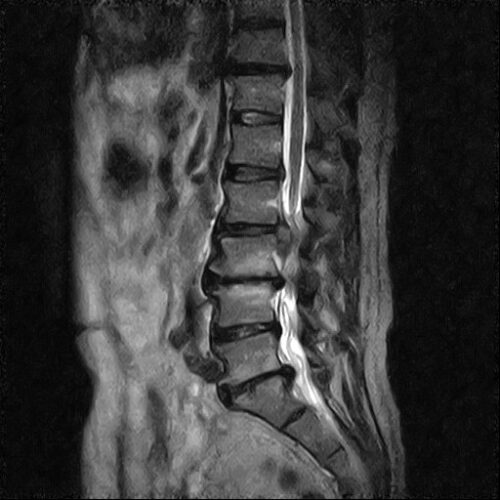

腰椎椎間板ヘルニア

・腰椎の椎体と椎体の間にある椎間板の一部が

変性、圧により突出した状態

・髄核、線維輪などが突出する

・突出した量や方向により症状が異なる